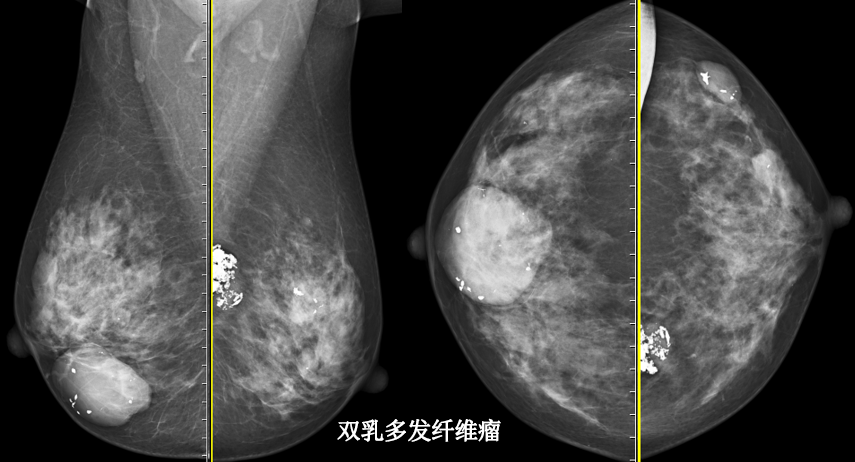

MG/CT: